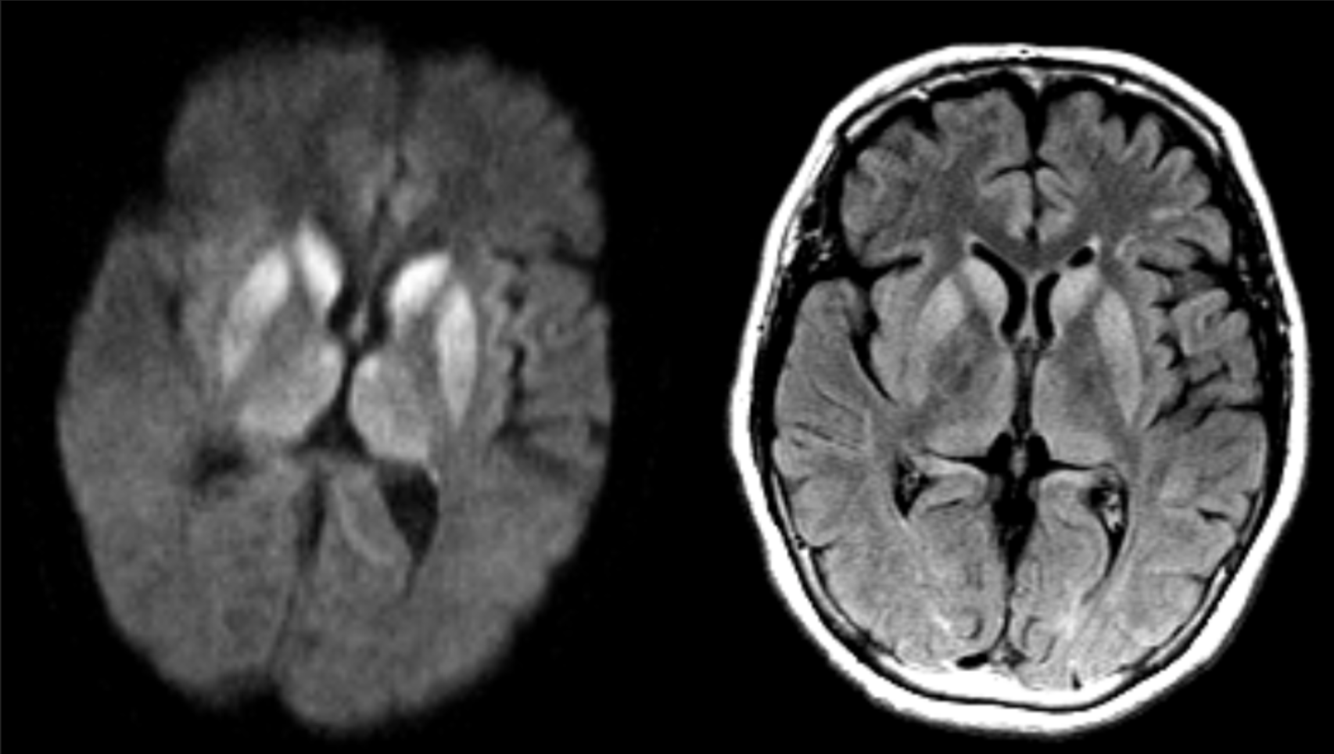

65 y/o M with dementia.

Creutzfeldt-Jakob Disease (CJD)